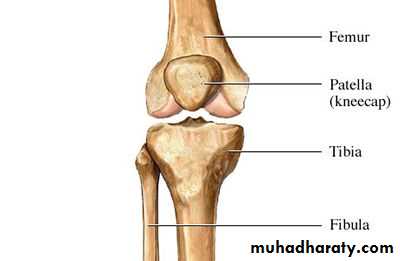

Combining form for Body SystemsSkeletal

• arthr/o joint• chondr/o cartilage

• cost/o rib

• crani/o skull

• ligament/o ligament

• my/o muscle

• muscul/o muscle

• myel/o bone marrow

• oste/o bone

• pelv/o pelvis

• vertebr/o vertebra